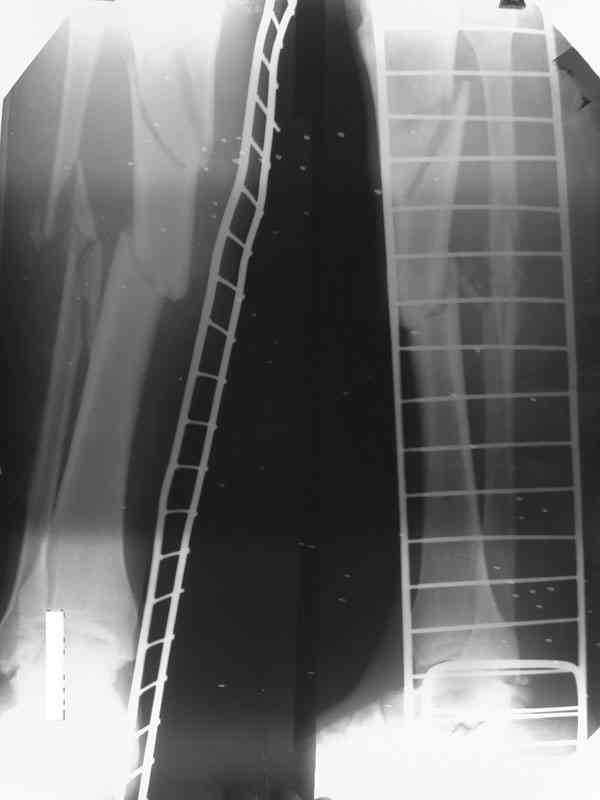

Re: Дефект и остеомиелит tibia

Как дополнение высылаю снимки и фото конечности, чтобы Вы могли оценить состояние м/т, и течение заболевания.

Доводим также к сведенью что дистальный межберцевый синастоз уже состоялся, ложный сустав малоберцевой кости в с/з. Учитывая так же отсутстаие нормального обеспечения больного в послеоперационном периоде мы склоняемся к аппарату внешней фиксации.

Хотелось бы уточнить позицию по д-зу на данный момент-Хронических заболеваний у пациента нет. Свищ по передней поверхности в проксимальном отделе дистального фрагмента до 3 мм. Выделения серозно- геморагического характера. Явных признаков воспааления м/т нет и не было на протяжении 4 мес.